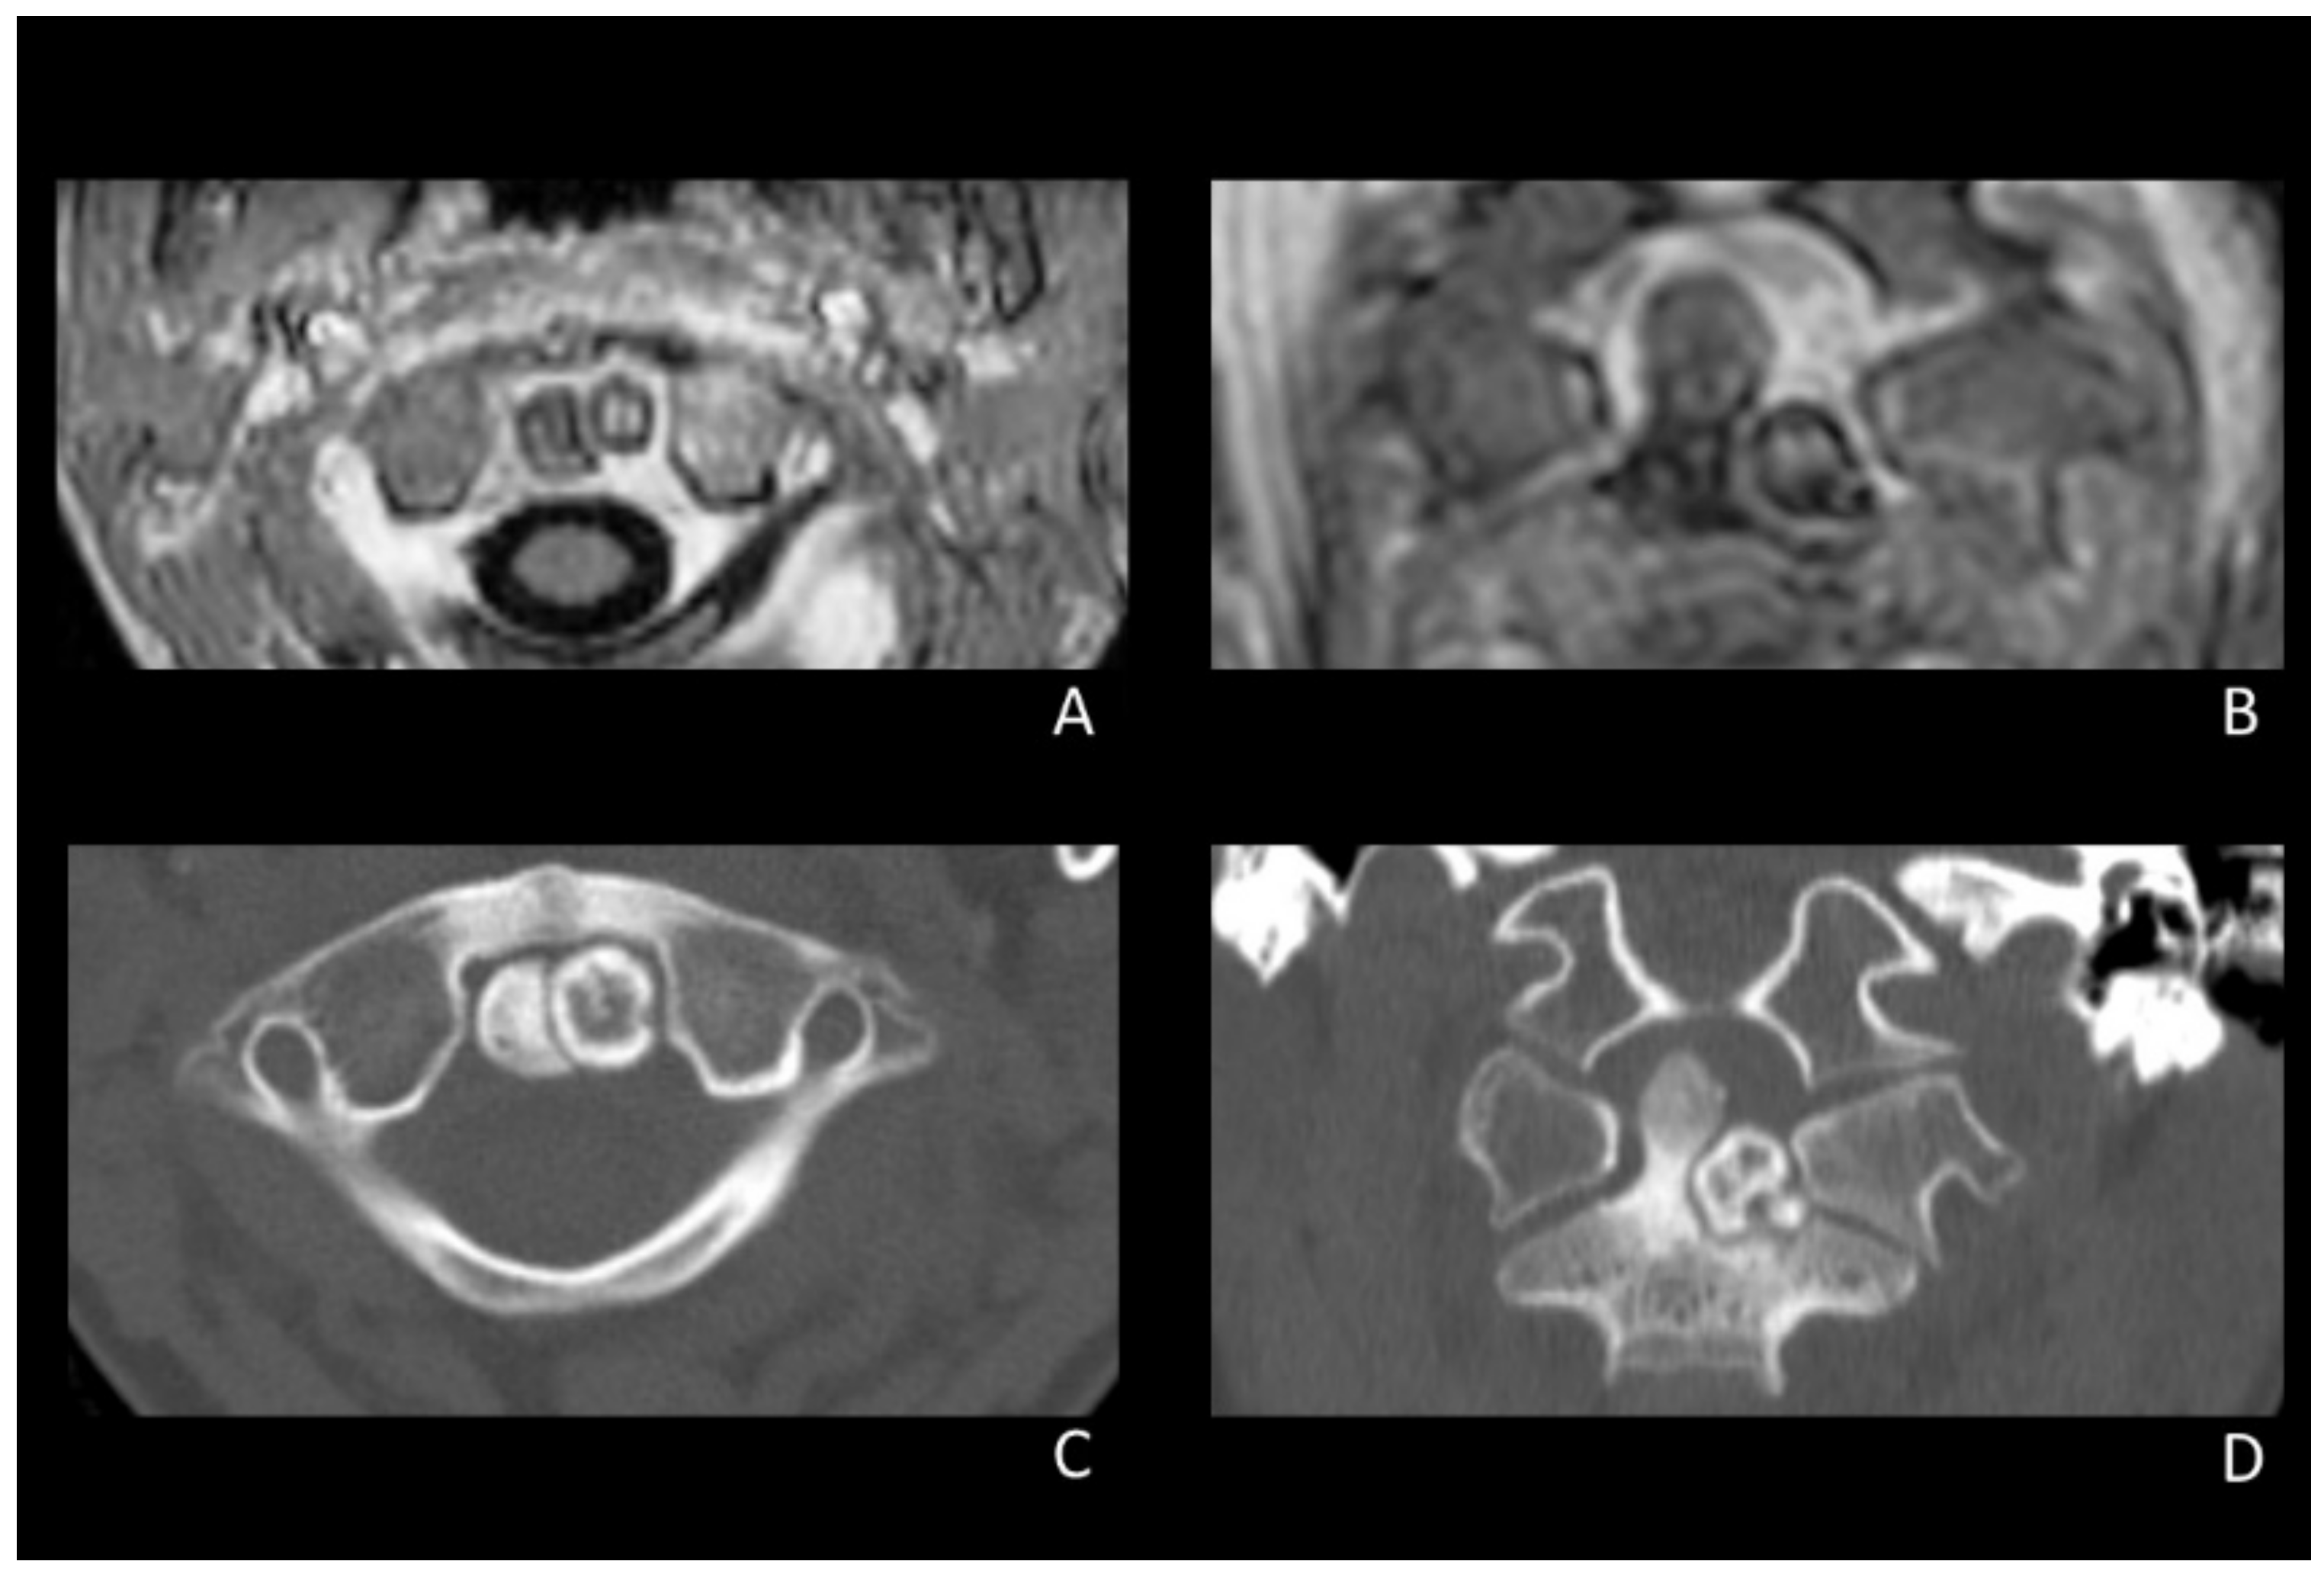

2.1. Technical Note

2.1.1. Clinical Presentation, Diagnosis, and Initial Conservative Therapy

2.1.2. Surgical Procedure